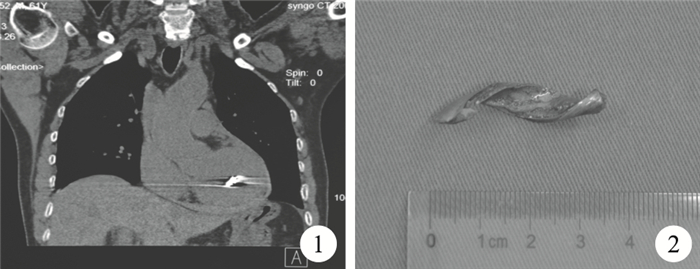

臨床資料??患者??男,61歲。入院前10 h被一金屬物飛濺擊中左胸前部,胸部CT示:心臟內有金屬異物,急診轉入我院。查體:血壓115/75 mm Hg,左側第5肋間鎖骨中線處見一傷口,長約1.5 cm,無活動性出血,心率101次/分,律齊,未聞及心臟雜音。急診胸部CT示:左心室金屬異物貫通傷,心包積液,左胸腔積液(圖 1)。術前準備后急診行開胸探查術,經胸骨正中切口進胸,見心包內有積血約200 ml,左心室前壁有血凝塊淤積。快速建立體外循環后清除血凝塊,見左心室前壁有一直徑約1.5 cm的破口,左心室后壁被一金屬物刺破,破口直徑約1.0 cm,金屬頂端將該破口堵塞。先經后壁破口內將金屬物輕柔螺旋形旋轉取出,測量金屬物長約3.5 cm,呈螺旋狀(圖 2)。用3-0 Prolene線帶墊片水平褥式縫合后壁及前壁破口。切開左側胸膜,清除左胸血性積液500 ml,留置引流管。術后第1 d心包引流1 700 ml,第2 d 800 ml,以后逐漸減少,于術后第7 d拔除引流管。術后患者發生肺部感染、低氧血癥,呼吸機支持6 d后脫機拔管,術后2周復查超聲心動圖提示心內結構形態功能正常,無心包積液,治愈出院。隨訪4個月,無明顯不適。

討論??心臟貫通傷多由盲管性火器傷所致,常見于右心室,往往引起致命性大出血或心臟壓塞,而在日常工作中所致的心臟貫通傷尤其是左心室貫通傷鮮見報道[1-2]。該患者術前不難診斷,入院時生命體征平穩,考慮與金屬物本身為螺旋形,入口細長,被血塊填塞后自行止血,而出口被金屬異物堵塞。對于心臟異物的治療方案及手術時機選擇存有爭議,該患者為心臟貫通傷,異物大且為污染物,隨時有死亡風險,需緊急手術。我們在對該例患者的救治過程中體會:(1)術前積極備血;(2)心包切開后先快速建立體外循環,再探查心臟;(3)手術切口因按照“就近、微創”的原則;(4)取出異物時應按照其形狀輕柔用力,避免脫落或加重心肌挫傷。該例患者左心室心肌損傷后出現反復心室顫動,血壓不穩,破口雖有效縫合,但滲血多,術后引流多,所幸備血充足。該患者左心室前后壁破口小,心內結構無法滿意探查(有條件的醫院可采用術中經心包和食管超聲心動圖等檢查了解心室內部情況,但我院目前尚無此條件),先挽救患者生命,后期加強隨訪也是一種有效的方法。